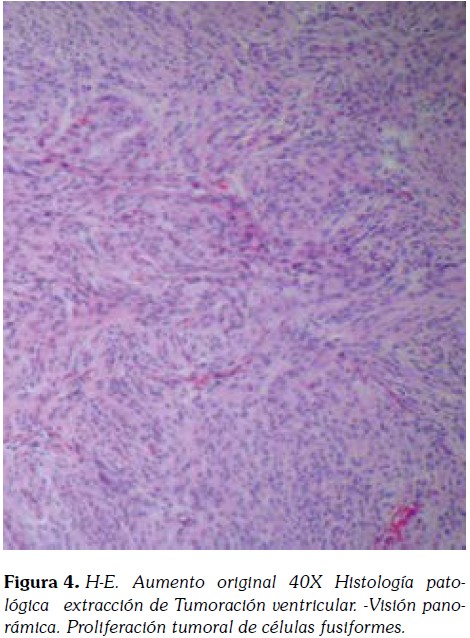

Histológicamente, el tumor fue reportado como formación por células dispuestas en racimos lobulados con zonas de espirales. Presencia de núcleos ovalados con cromatina fina granular y Actividad mitótica baja. Por inmunohistoquímica, las células mostraron una fuerte positividad para el antígeno de membrana epitelial. El diagnóstico final fue meningioma meningotelial.

Macroscópicamente, se evidencia una muestra fragmentada de 4x3x1cm constituida por porciones de un tejido homogéneo, blanquecino y grisáceo de aspecto fasciculado y consistencia intermedia. Histológicamente, los hallazgos correspondían a un meningioma convencional de patrón predominantemente meningotelial (4, 9,10).

El tumor presentaba una microarquitectura lobular constituida por células eosinofílicas de configuración sincitial, con bordes mal delimitados, y núcleos redondeados u ovales con nucléolos poco prominentes (Figura 4 , 5).